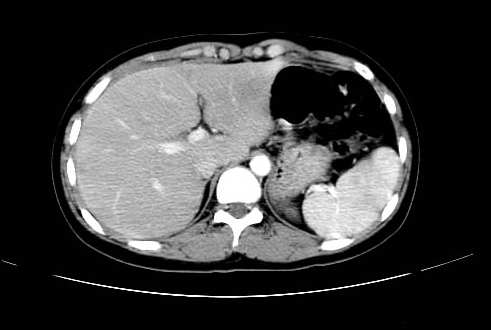

女 16岁  右上腹痛一天,无其他不适

肿块最大径位于十二指肠降段与水平段移行处,并且与肝脏压迹呈“0”形征,可以考虑位于肝外并与胃肠道关系紧密,考虑胃肠道间质瘤(gist)可能较大,须除外神经节起源肿瘤。

肿块与十二指肠关系密切,支持间质瘤诊断.肝脏与结肠均为受压改变.

我坚决反对您的观点,该病例定位:横结肠肝曲与升结肠之间的肠系膜及部分肠壁。请看下图:

病灶巨大,少部分向肠腔内生长,大部分向长腔外生长。其密度不均匀,增强显示明显不均匀强化,并见有大片状始终不强化的不规则坏死液化区。虽然病灶中上部形态尚可,病人又如此年轻,但中下部形态、密度、强化特点强烈提示为恶性病灶。综上,我考虑本病例为:恶性胃肠道间质瘤。